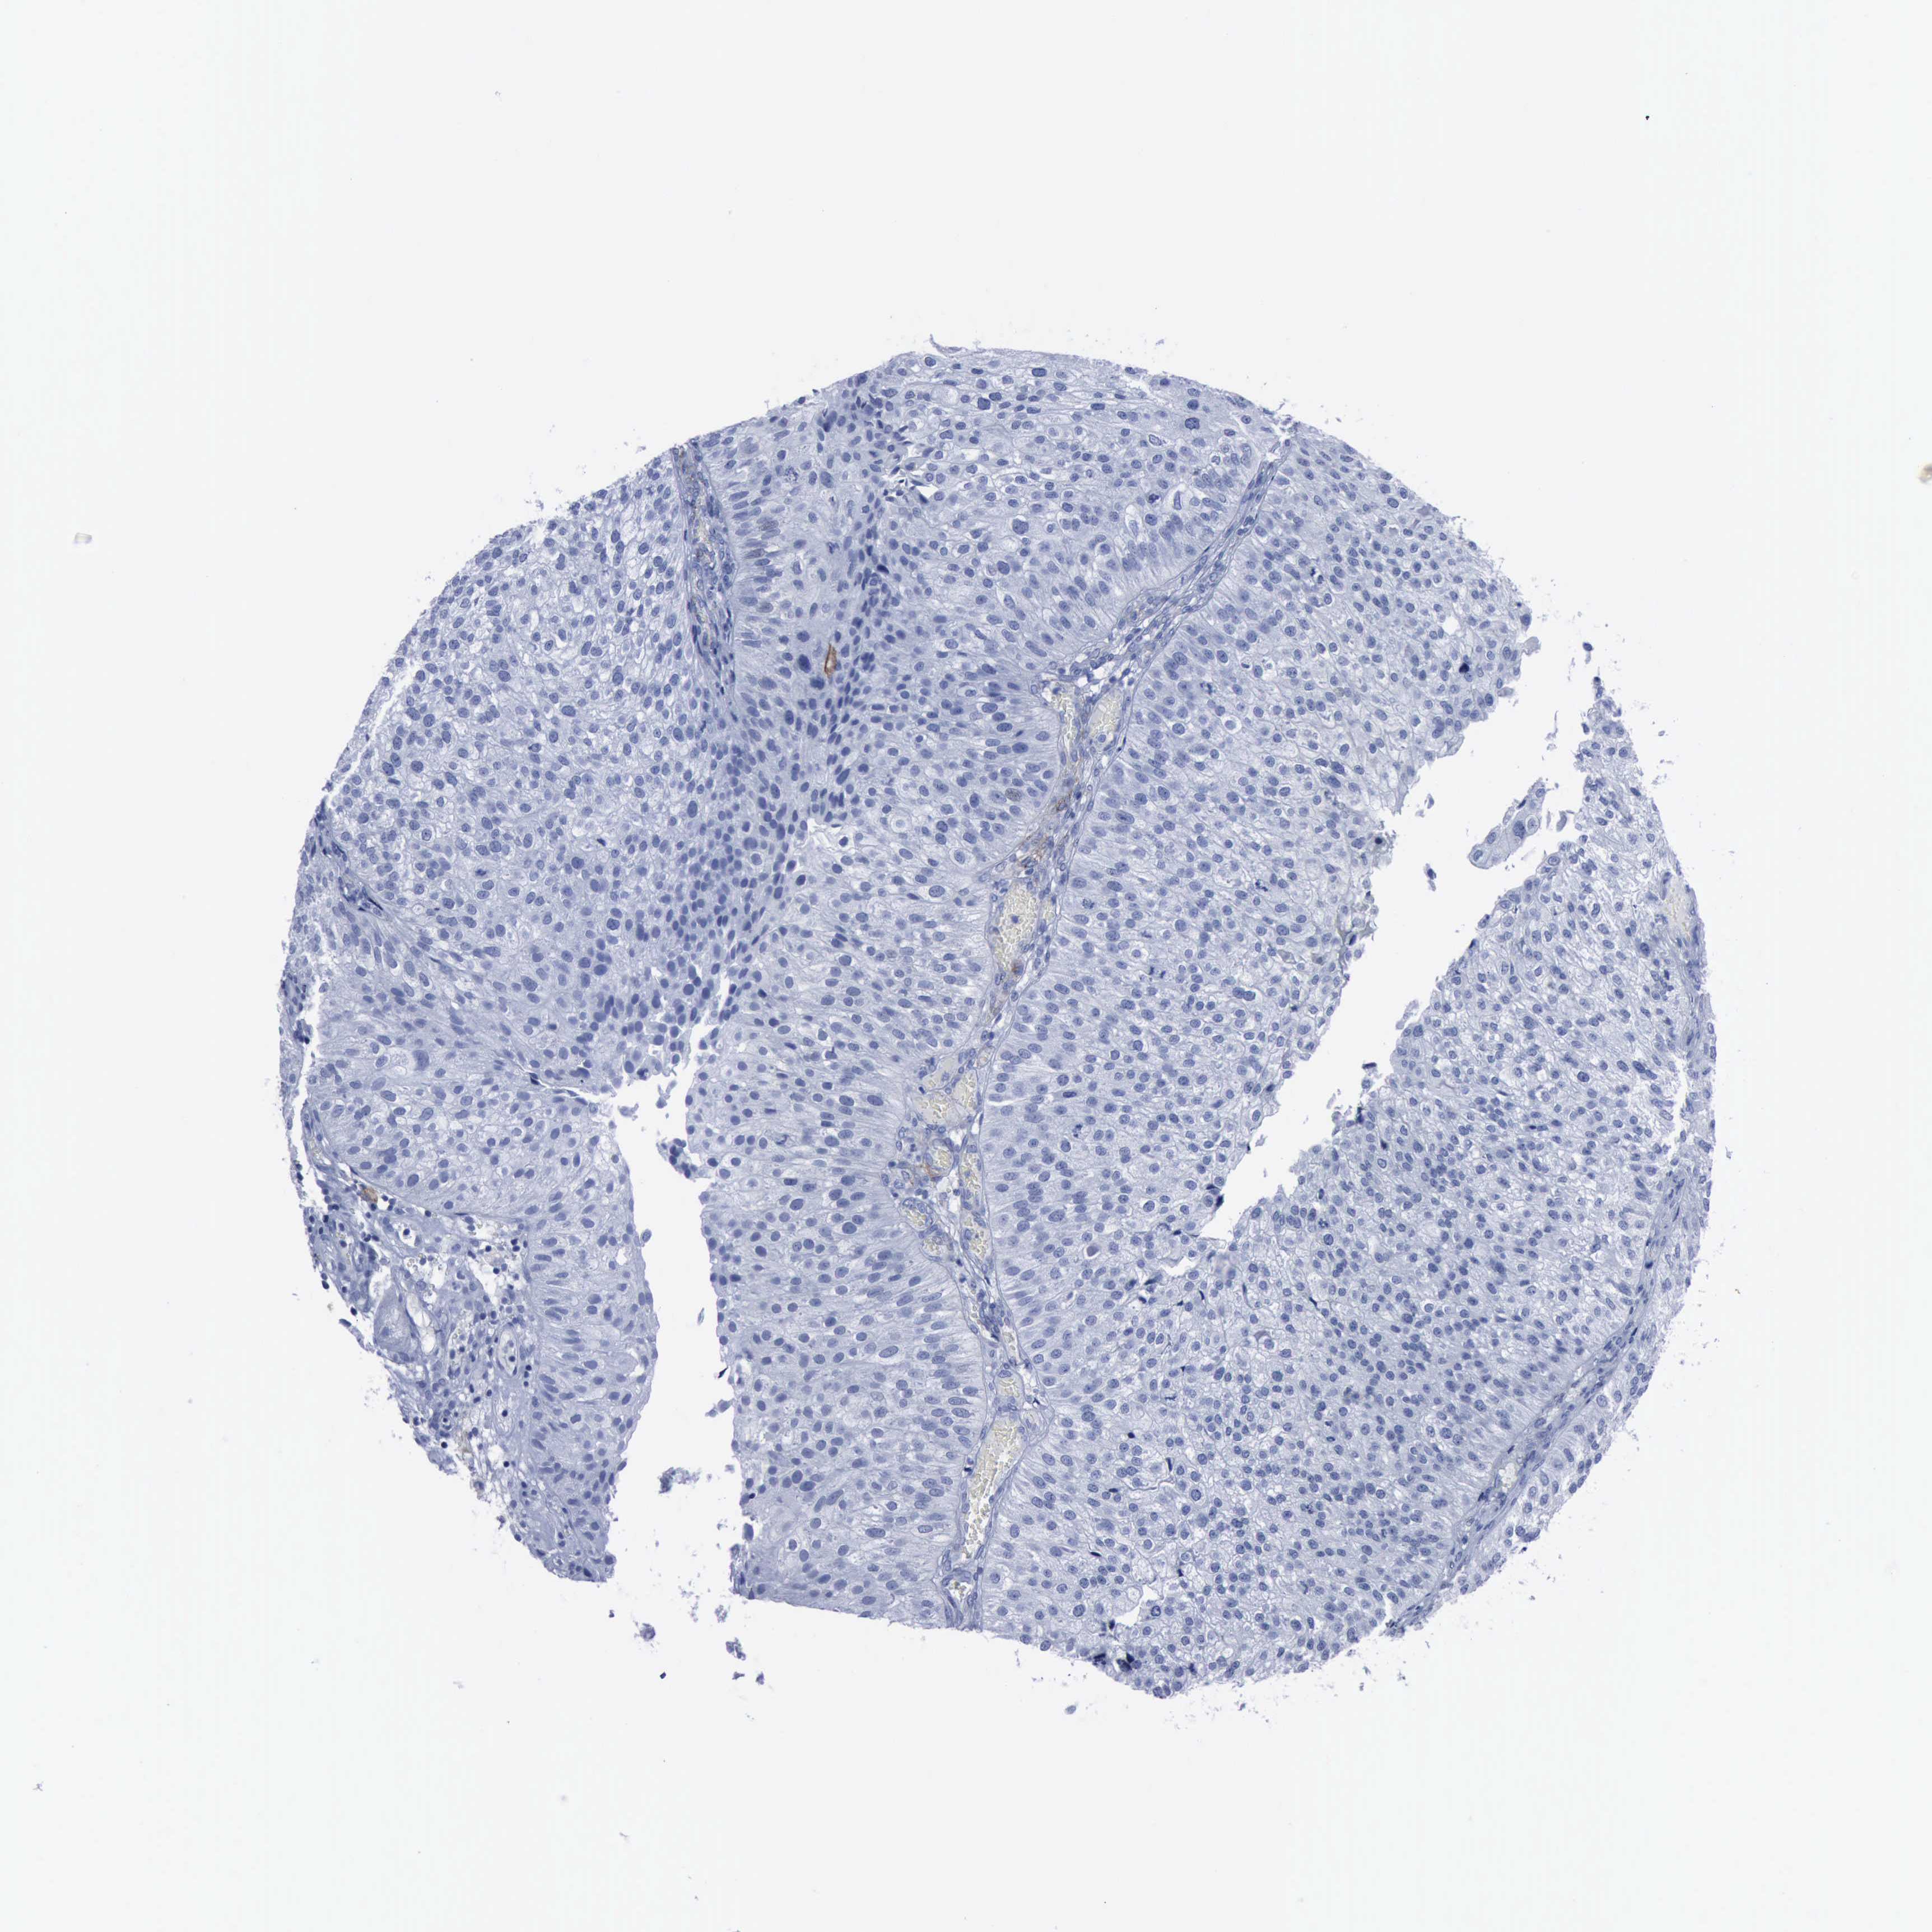

UROTHELIAL CANCER - Protein expressioni

A mouse-over function shows sample information and annotation data. Click on an image to view it in a full screen mode. Samples can be filtered based on level of antibody staining by selecting one or several of the following categories: high, medium, low and not detected. The assay and annotation is described here.

Antibody stainingi

Antibody staining in the annotated cell types in the current human tissue is reported as not detected, low, medium, or high, based on conventional immunohistochemistry profiling in selected tissues. This score is based on the combination of the staining intensity and fraction of stained cells.

Each image is clickable and will lead to virtual microscopy that enables deeper exploration of all samples and also displays staining intensity scores, fraction scores and subcellular localization as well as patient and tissue information for each sample.

Antibody HPA004765

Antibody CAB000143

Antibody CAB001995

Staining

High

Medium

Low

Not detected

Intensity

Strong

Moderate

Weak

Negative

Quantity

>75%

75%-25%

<25%

None

Location

Nuclear

Cytoplasmic/membranous

Cytoplasmic/membranous,nuclear

Urothelial carcinoma, High grade